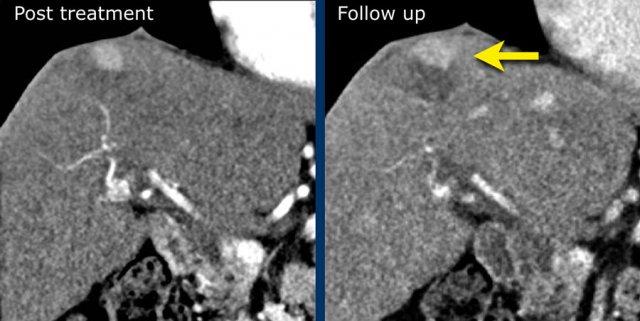

LRTR không còn khả năng sống

Các tổn thương ngấm thuốc thì động mạch đã được điều trị bằng DEB-TACE. Trên hình ảnh theo dõi ghi nhận tình trạng ngấm thuốc nhẹ quanh tổn thương, đây là hình ảnh bình thường sau điều trị.

LRTR không xác định

Hình thái ngấm thuốc không điển hình so với hình thái ngấm thuốc đặc trưng sau điều trị và không đáp ứng tiêu chí của phân loại có thể còn sống hoặc chắc chắn còn sống.

Đối với một số phương pháp điều trị, hình thái ngấm thuốc sớm sau điều trị có thể không phân biệt được một cách đáng tin cậy giữa khối u còn sống và không còn sống, do đó phân loại phù hợp nhất trong giai đoạn sớm sau điều trị này có thể là LRTR không xác định.

Vùng ngấm thuốc thì động mạch không có thải thuốc trong vùng hoại tử sau đốt sóng tại phân thùy 5 (mũi tên), phân loại LRTR không xác định.